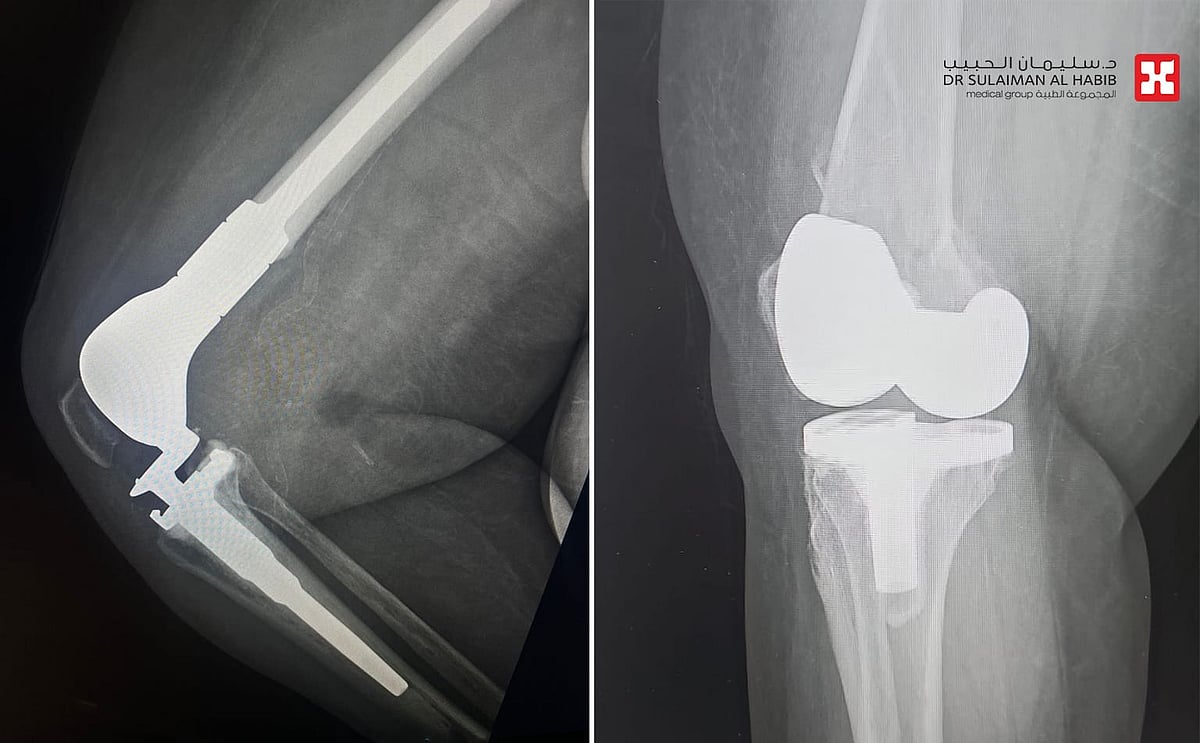

مستشفى الدكتور سليمان الحبيب بالسويدي يستبدل عظمة الفخذ بعملية متقدمة ويعيد “الحركة” لمسنة

شهد مستشفى الدكتور سليمان الحبيب بالسويدي، إجراء عملية متقدمة لاستبدال الجزء السفلي من عظمة الفخذ Distal Femoral Replacement, DFR لسيدة تبلغ من العمر”80″ عاماً، كانت قد خضعت لعملية استبدال مفصل ركبة قبل عامين، وتعرضت مؤخراً لحادث منزلي عرضي، نتج عنه كسر في أسفل عظمة الفخذ، وعانت من أعراض حادة. ذكر ذلك د. رغيد شبو استشاري جراحة العظام والإصابات واستبدال المفاصل رئيس الفريق الطبي المعالج.